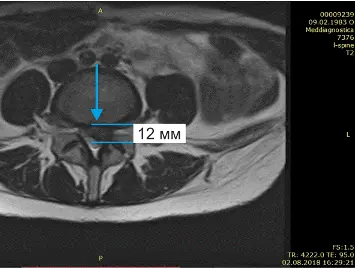

Бывают случаи, когда вправление грыжи можно провести за несколько сеансов. Иногда даже за один. Это возможно при протрузии диска и грыже небольшого размера. Если же грыжа большая и сопровождается болью в ноге, то для излечения понадобится курс лечения. Как это было с одной из наших многочисленных пациентов Ириной, результаты чего видны на МРТ, что ниже.